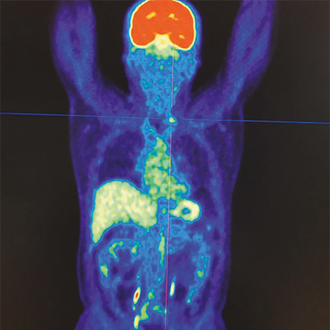

Променева діагностика, променева терапія

Лікування інгібіторами тирозинкінази пацієнтів з метастатичним диференційованим раком щитоподібної залози, рефрактерним до радіойодотерапії